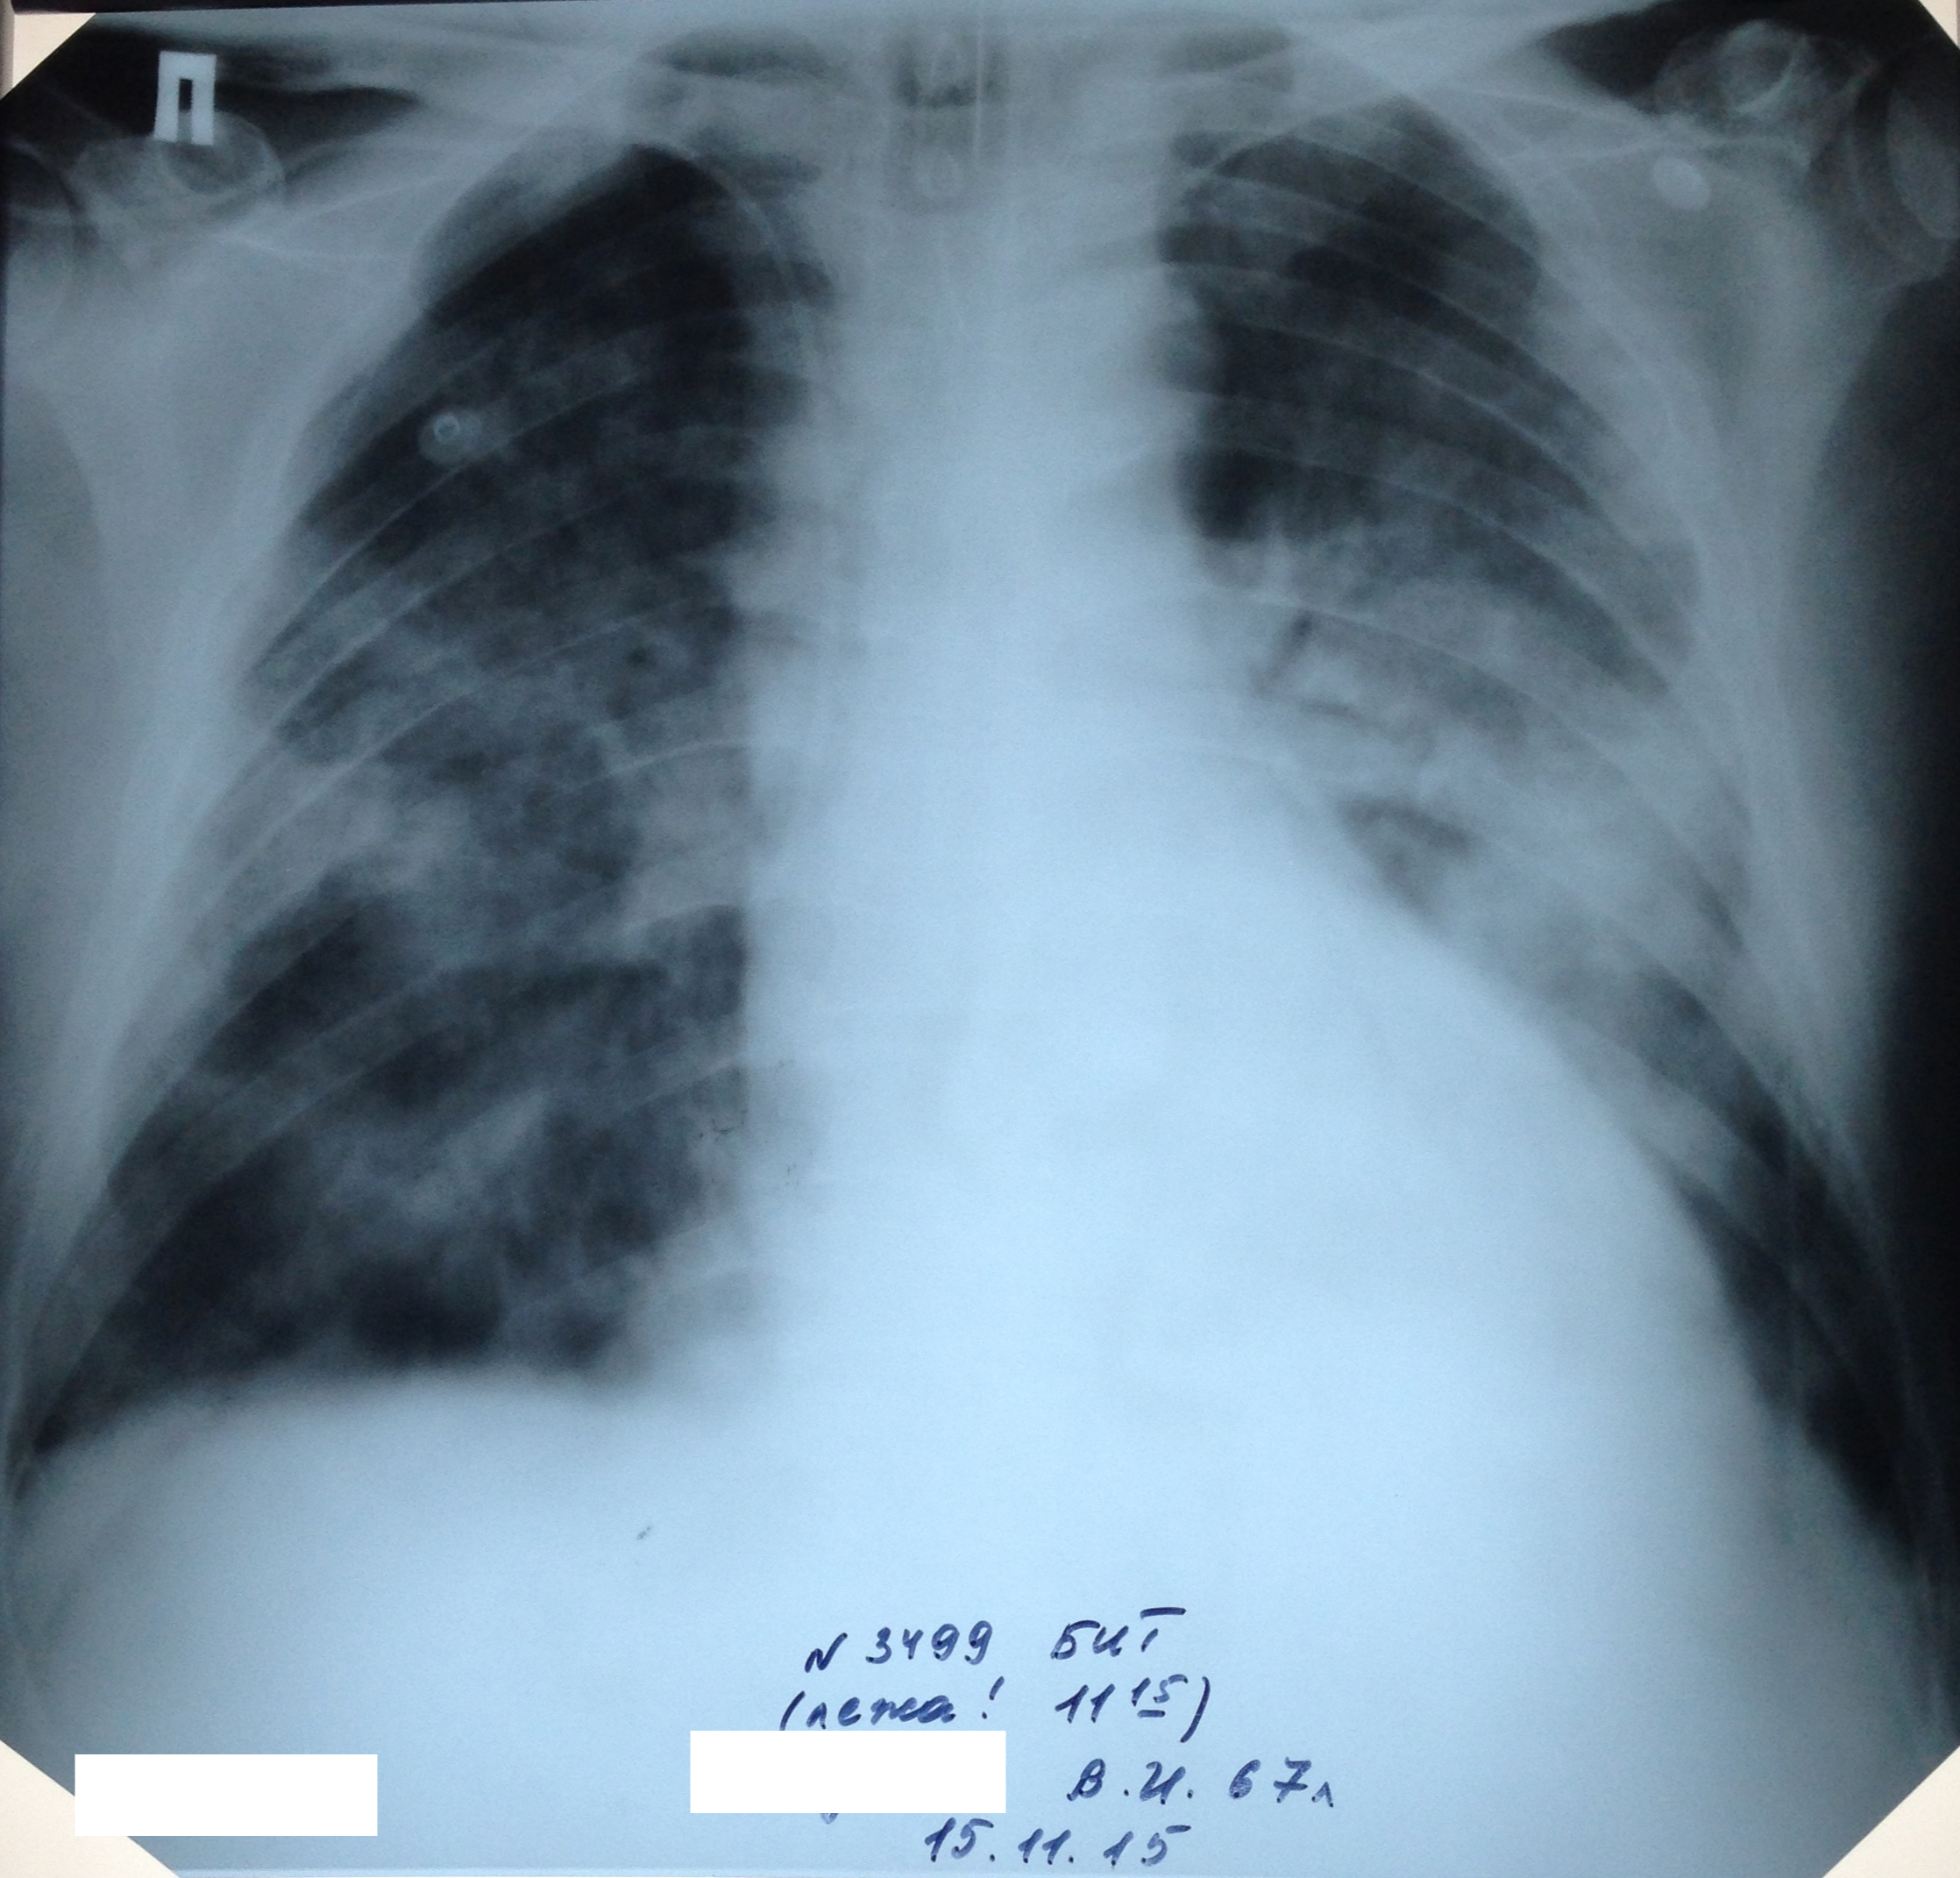

Динамика пневмонии у мужчины 67 лет с миеломной болезнью

Вложения:

1-.jpg

1-.jpg [ 1.24 MiB | Просмотров: 53561 ]

2-.png

2-.png [ 6.42 MiB | Просмотров: 53561 ]